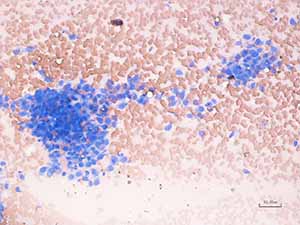

An image of a direct smear from the fine-needle aspirate is shown. (You may select only one option.)

Which of the following is a correct interpretation of the cytology?